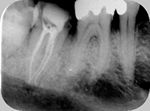

◆根管治療

むし歯等で歯の神経が死んでしまった場合に必要となる根の治療です。

根管治療X線写真